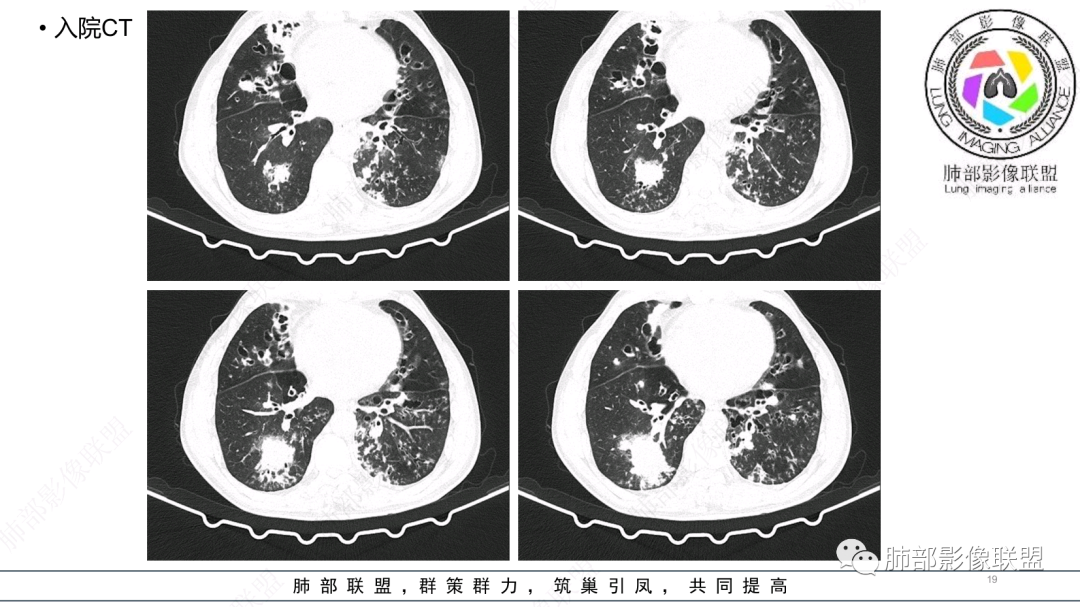

56岁,工作性质:环卫工人。主诉:咳、痰、喘、发病一周。急性起病(或者慢病+AE),呼吸道感染症状。化验指标白细胞、中性、CRP明显升高。影像学显示多灶性,有柱状支扩,囊状支扩等结构肺病,责任细菌主要考虑铜绿假单胞菌,不排除合并其他细菌以阴杆为主;存在树芽影,发热,炎症沿支气管束分布,是否合并TB?真菌?;树芽伴发热支原体感染也要需要考虑进去;全肺多灶性炎症,部分病灶周围有晕,右上叶疑似反晕,内部疑似有丝,右下肺考虑存在粘液栓,加之环卫工工作性质,考虑霉菌,主要考虑曲霉。

两肺支扩,两肺沿支气管分布多发结节、树芽及团块,边缘模糊,部分支气管管壁增厚,考虑气道侵袭性曲霉菌,鉴别铜绿、奴卡、结核。

有肉芽肿,铜绿就不考虑了。曲霉有肉芽肿就三种类型:侵袭性曲霉中的血管侵袭,慢性中的单纯结节及半侵袭性曲霉。所以曲霉不考虑,有纤维化也不支持。那就剩三个疾病:奴卡、结核、NTM。影像都挺符合的。但WBC及PCT那么高,结核及NTM就明显不符合了。

多发结节,部分结节边缘清楚,部分边缘模糊,支扩合并肉芽肿性炎,奴卡菌与曲霉之间选择。

影像改变为支扩伴气道来源感染,部分实变性伴有小脓肿及钙化,结合PCT及白细胞、中性粒明显增高,符合细菌感染,首先考虑奴卡,绿脓次之,因为临床有喘息、影像实变性有钙化,加上环卫工这一职业史,需要鉴别曲霉或奴卡合并曲霉。

支扩伴发的铜绿主要是支气管周围的渗出改变,不会伴有肉芽肿改变,但是如果是长期反复慢性感染的铜绿合并一些机化的时候影像上也可以类似肉芽肿,但是这种很少见,而且机化一般会有纤维化,也容易与肉芽肿区分,而支扩伴发奴卡即可以有渗出,也可以有肉芽肿和慢性或亚急性脓肿出现,所以今天这个肯定是考虑奴卡的。